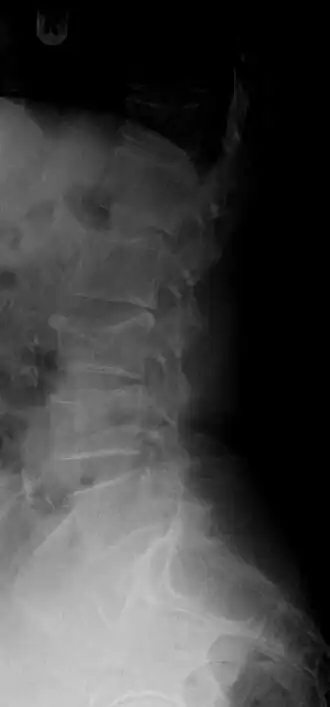

Zijdelingse röntgenfoto van de wervelkolom, waarop een compressiefractuur van L3 (de derde lendenwervel) zichtbaar is. (Midden in beeld.) Het lichaam (corpus) van de wervel is als het ware in elkaar gedrukt, waardoor de vorm van de wervel duidelijk anders is geworden. | ||||

Een compressiefractuur[1] is een botbreuk die voorkomt in bijvoorbeeld een wervel, als deze nog niet gehard is. Deze breuk komt veel voor (voornamelijk bij vrouwen) ten gevolge van osteoporose. Het bot wordt bij een compressiefractuur als het ware in elkaar gedrukt.